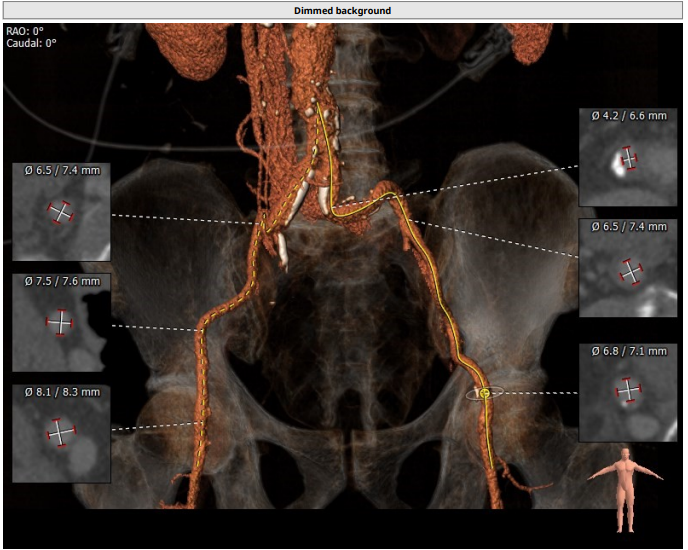

入路情况:

主动脉弓部走行欠佳,主动脉弓部三根毛开口未见明显狭窄征象、未见发育变异,胸主动脉、腹主动脉走行迂曲、未见明显钙化斑块,管腔未见明显狭窄,双侧髂动脉-股动脉走形稍迂曲,管腔未见明显狭窄,综合考虑,推荐右侧股动脉做为主入路。右侧股动脉穿刺水平管腔直径约为 8.2 mm,右侧股动脉分叉约在股骨头下缘水平。

经南方医科大学顺德医院心血管内科黎文生主任团队分析研判,结合患者入路情况,以右股动脉为主入路,术中操作轻柔,预选 18 mm 球囊预扩,观察球囊腰征及反流情况,优选 VenusA23 号瓣膜进行植入,时刻观察左右冠灌注情况,释放完瓣膜后超声、造影评估效果。